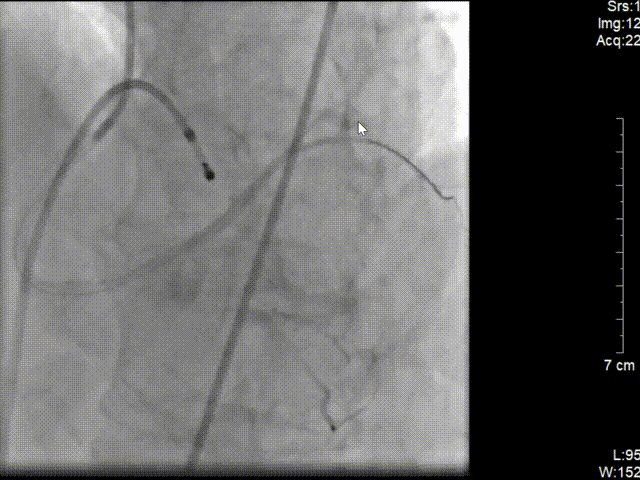

A. 心电图提示急性下壁心肌梗死,合并III°房室传导阻滞,考虑罪犯血管为右冠可能性大;

B. 患者在消毒铺巾时突发意识障碍,心电监护示室颤,予电除颤后意识恢复,心电图仍提示下壁心肌梗死,III°房室传导阻滞;

C.立即穿刺股静脉行临时起搏器植入;